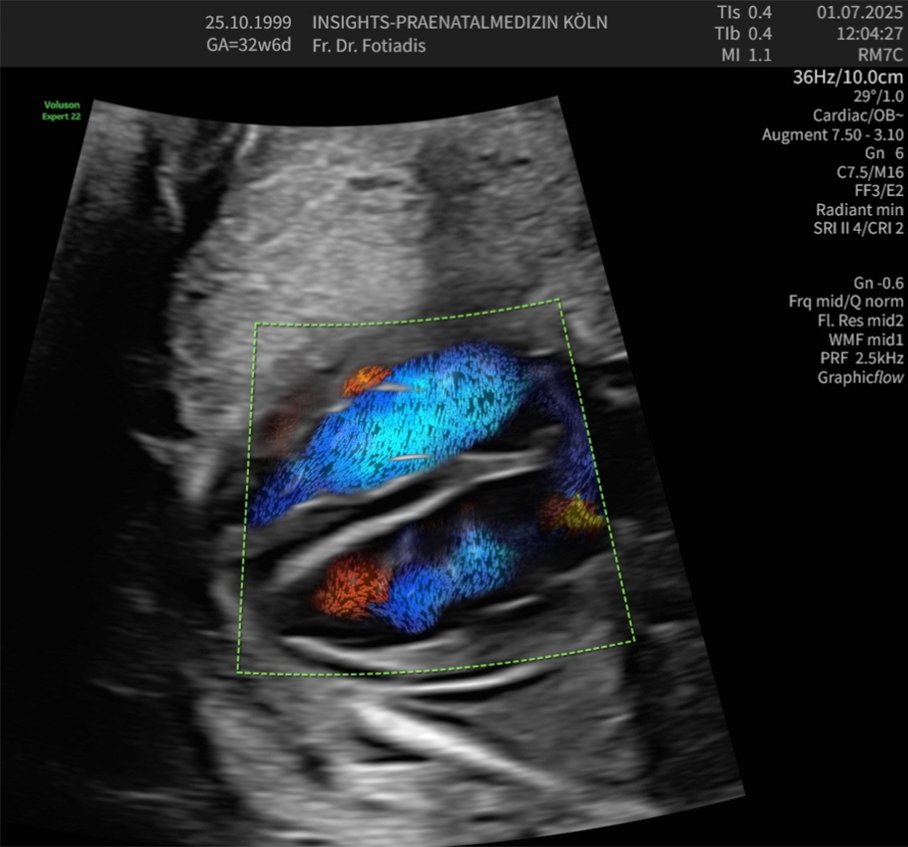

Echokardiographie

Fehlbildungen des Herz-Kreislaufsystems gehören zu den häufigsten Störungen des Neugeborenen und finden sich bei 0,5–1 % aller lebend geborenen Kinder.

Viele dieser Herzfehler sind nicht schwerwiegend und bedürfen keiner Therapie. Ein Teil jedoch kann gravierend, ja sogar lebensbedrohend bei der Geburt sein, sodass hier die Diagnose schon im Mutterleib lebensrettend sein kann. In diesen Fällen muss dann die Entbindung geplant in einem Zentrum mit den Neonatologen und Kinderkardiologen stattfinden, das Neugeborene benötigt bestimmte Medikamente oder muss intensivmedizinisch betreut werden. Manchmal sind auch sehr schnell Eingriffe und Operationen nötig.

Das Entdecken und die Beurteilung von fetalen Herzfehlern erfordert ein hohes Maß an Untersuchungserfahrung und eine entsprechende Geräteausstattung, sodass sie häufig im Rahmen von Routineuntersuchungen nicht erkannt werden. Daher sollten gerade Eltern mit einem erhöhten Risiko für fetale Herzfehler diese Untersuchung des kindlichen Herzens durchführen lassen.

Alle Untersuchungen werden an High-end-Geräten durchgeführt, die technisch auf dem allerneuesten Stand sind.